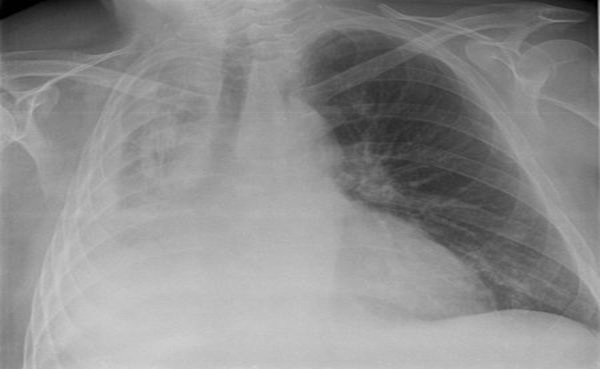

무기폐의 증상은 무기폐의 범위, 발생 속도, 기저 질환 등에 따라 다양하게 나타납니다. 작은 범위의 무기폐는 증상이 없을 수 있지만, 넓은 범위의 무기폐는 심각한 호흡 곤란을 유발할 수 있습니다. 급성으로 발생한 무기폐는 호흡 곤란, 흉통, 기침, 쌕쌕거림, 청색증 등의 증상을 동반할 수 있으며, 만성적으로 진행된 무기폐는 호흡 곤란, 만성 기침, 가래 등의 증상을 유발할 수 있습니다. 무기폐의 가장 흔한 증상은 호흡 곤란으로, 숨을 쉬기 어렵거나 답답한 느낌이 들 수 있습니다. 흉통은 무기폐가 발생한 부위에 통증이 느껴지는 증상이며, 기침은 기관지가 자극되어 발생할 수 있습니다. 쌕쌕거림은 좁아진 기도를 통과하는 공기 때문에 발생하는 소리이며, 청색증은 혈액 내 산소 부족으로 인해 피부가 푸르게 변하는 증상입니다. 무기폐는 흉부 X선 촬영, CT 촬영, 기관지 내시경 등을 통해 진단할 수 있습니다. 흉부 X선 촬영은 폐의 허탈 여부를 확인하는 가장 기본적인 검사이며, CT 촬영은 무기폐의 원인과 범위를 보다 정확하게 파악하는 데 도움을 줍니다. 기관지 내시경은 기관지 내부를 직접 관찰하고, 필요한 경우 조직 검사나 이물질 제거를 시행할 수 있는 검사입니다. 무기폐는 다양한 원인에 의해 발생할 수 있으므로, 정확한 진단을 통해 원인 질환을 파악하고 적절한 치료를 받는 것이 중요합니다.